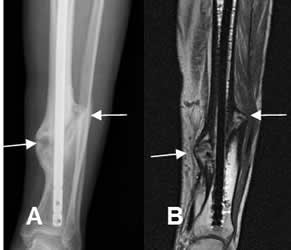

Fig 87. Callo perióstico.

A: Rx AP. Fractura de la tibia estabilizada con clavo de Kuntcher. Clínicamente está consolidada, pero persiste línea radiolúcida entre los extremos.

B: RM coronal en T1 y C: RM coronal en STIR. Callo óseo continuo, sin cambios inflamatorios.